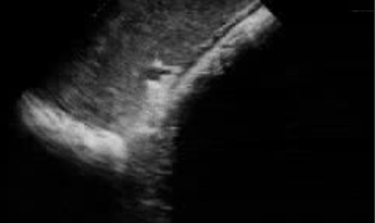

Een bloedonderzoek toont aan dat de leverwaarden niet optimaal zijn. Een gerichte anamnese en en inspectie van de omgeving (toxische stoffen, voeding, aanwezigheid andere dieren....) is zeer belangrijk bij de aanpak van een leverprobleem. een echografie van de lever kan soms de oorzaak van het leverprobleem aantonen (abces, verstopte galgangen, steentjes of gruis, gezwollen ontstoken lever, tumor). Lees het artikel over leverproblemen bij paarden.....

Paarden kunnen uitzonderlijk een nierprobleem hebben. Echografie van de nieren, al dan niet gecombineerd met een endoscopie van de urinewegen kan een meerwaarde zijn om de oorzaak van het probleem aan te pakken.